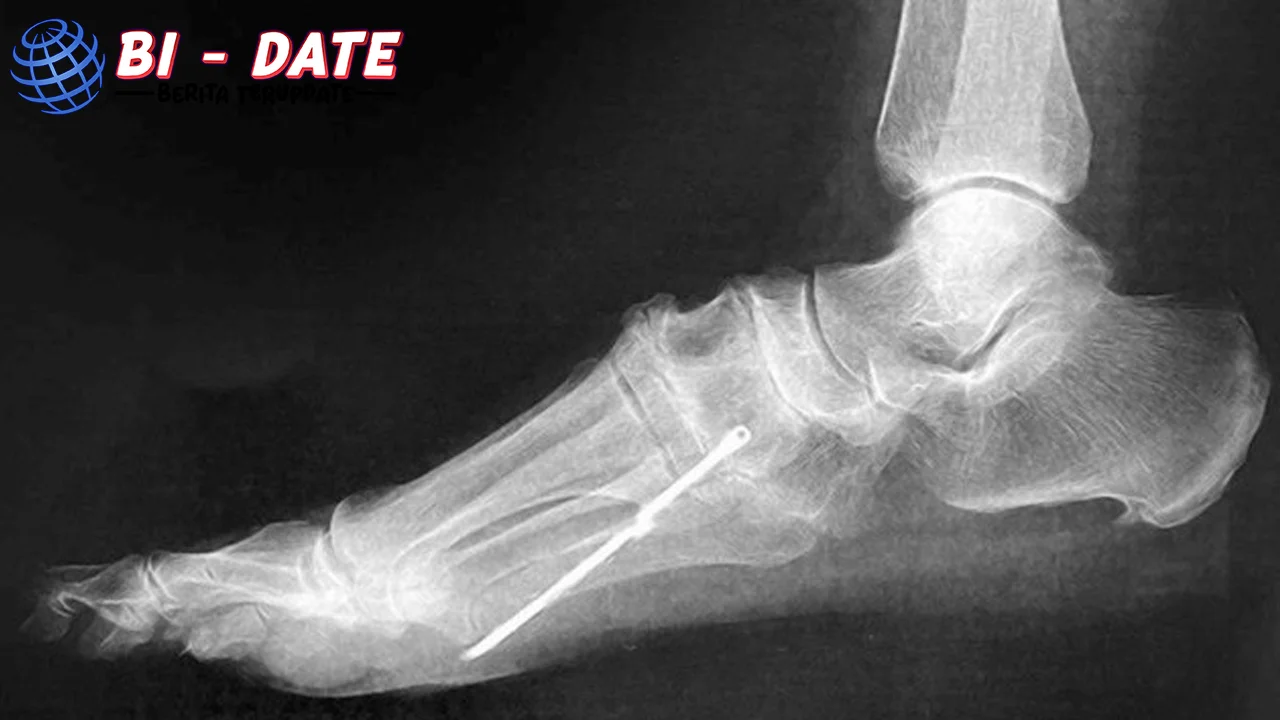

Suatu hari, dokter yang merawat Andi memutuskan untuk melakukan pemeriksaan lebih detail menggunakan teknologi imaging yang lebih canggih. Hasilnya mengejutkan. Ternyata ada sebuah benda logam kecil tertanam di kaki Andi, tepat di dekat tulang betis. Benda ini telah menyebabkan iritasi jaringan sekitarnya, memicu peradangan, dan menimbulkan rasa kronis.

Setelah diskusi mendalam dengan tim medis, Andi menjalani prosedur kecil untuk mengangkat benda logam tersebut. Prosedur ini berjalan dengan lancar, dan tim dokter memastikan tidak ada komplikasi lebih lanjut.